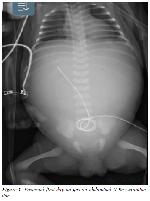

On the third postoperative day, while the proximal esophagus was aspirated, it was observed that the orogastric tube reached the stomach. At first, it was tho-ught that the reason for the orogastric not reaching the stomach was the disruption of the His angle after excessive gastric dilatation. The patient was started on oral feeding on the 5th postoperative day and passed stool thereafter (Figure 5).

Click Here to Zoom

Figure 5: Postoperative seventh days, Orogastric tube.